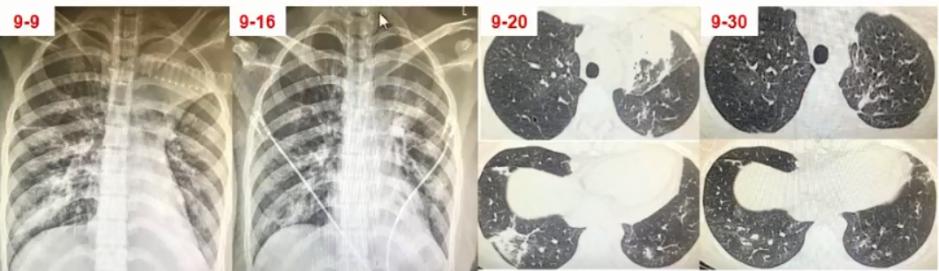

病例3

男,37岁,既往身体健康。因发热、咳嗽、咳黄痰1周入院。

日最高体温38.8℃-39.5℃,伴咽痛、肌痛、全身乏力,急诊血常规

WBC:8.74×109/L,N:0.865,予退热胶囊、头孢曲松、阿奇霉素等药物治疗3天无效。

CRP 12.10 mg/dl、PCT 0.107 ng/ml。

血清肺炎支原体抗体、肺炎衣原体抗体、军团菌抗体、流感病毒IgM均阴性。RT-PCR肺炎支原体核酸阳性。使用莫西沙星治疗14天后出院。

图3 双肺弥漫性小结节为主,中下肺布满粟粒样小结节,部分融合成片状

病原学诊断和转归

1. 病原学诊断

(1)入院次日BALF肺炎支原体核酸阳性

(2)血清肺炎支原体抗体,入院前为小于1:40;入院第14天为1:1280。

2. 转归

莫西沙星单药治疗2周后肺部阴影明显吸收

3. 诊断治疗面临的困难

• 临床表现不典型:咳黄痰

• 特殊的影像表现:中下肺弥漫小结节影

• 早期病原学检测无阳性发现

• 常规经验性治疗无效